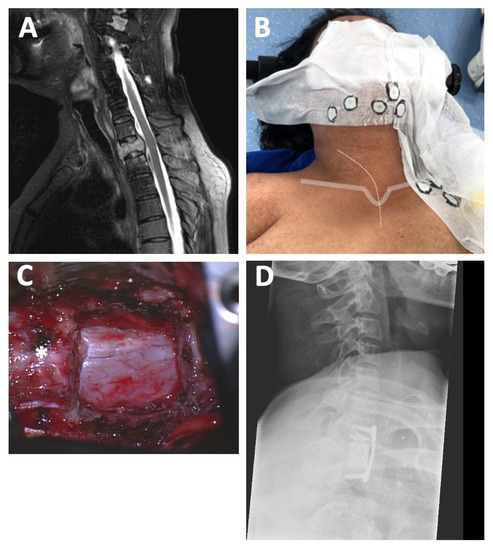

Spinal metastases. (A) Preoperative MRI of the CTJ showing a metastatic osteolytic lesion of T1 with an accompanying pathologic fracture (SINS 16). (B) Intraoperative landmarks for anterior access: skin incision (dotted grey line) starting at the level of the larynx follows the medial border of the sternocleidomastoid muscle towards the jugulum (solid grey line) and extends to the upper third of the sternum medially. CT-opaque fiducials (circled in black) were used for navigation guidance in this case using an intraoperative CT scan of the cervicothoracic junction. (C) Intraoperative microscopic view after complete T1 corpectomy and tumor removal with wide exposition of the dura (* indicates C7 vertebra). (D) Postoperative X-ray illustrating excellent implant position after standalone anterior treatment.

3.4. Case Illustration 1: Spinal Metastases

A 43-year-old female with a history of breast cancer presented at our department with increasing localized cervical and thoracic pain deteriorating with axial loading. The neurological examination revealed left-sided hypesthesia in the supply area of the C8 nerve root. In the subsequent full-spine CT and MRI imaging, a metastatic osteolytic lesion with paravertebral tumor involvement (T1) with an accompanying pathologic fracture was observed, resulting in a SINS of 16 with more than 50% collapse of the vertebral body and massive kyphosis of the CTJ, indicating spinal instability (Figure 1A).

Due to the underlying condition, the patient was given an ASA score of three, which led to the choice of an anterior access route for T1 corpectomy, tumor debulking, and fusion in a standalone concept in this patient. Anterior fusion from C7 to T2 without posterior fusion of the CTJ was achieved in this case. Postoperatively, the patient recovered completely from the C8 hypesthesia and loading pain and was discharged home after one day in the ICU and a total of 8 days in the hospital. The adjuvant chemotherapy and local radiation of the spine could begin three weeks after surgery. Despite the favorable initial course, the patient died from further systemic hepatic and pulmonary metastatic disease one year after the procedure.

Figure 1 shows representative pre- and post-operative images of this case as well as landmarks for skin incision.